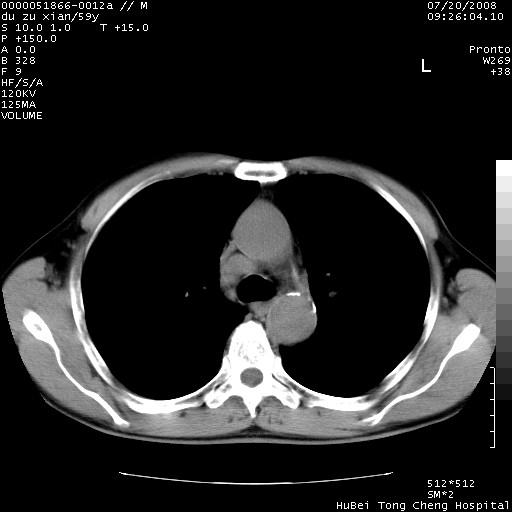

以下是引用宇宙ct在2008-8-25 23:21:00的发言:[br]右肺周围性肺癌并肋骨转移,纵隔淋巴结转移。

以下是引用zsl6918在2008-8-25 22:40:00的发言:[br]右肺周围性肺癌并肋骨转移,纵隔淋巴结转移。

以下是引用zy_zj在2008-8-26 15:24:00的发言:[br]单从病变本身,我倾向良性炎性病变,但肋骨转移了,所以说是考虑右肺周围性肺癌并肋骨、纵隔淋巴结转移可能性大。